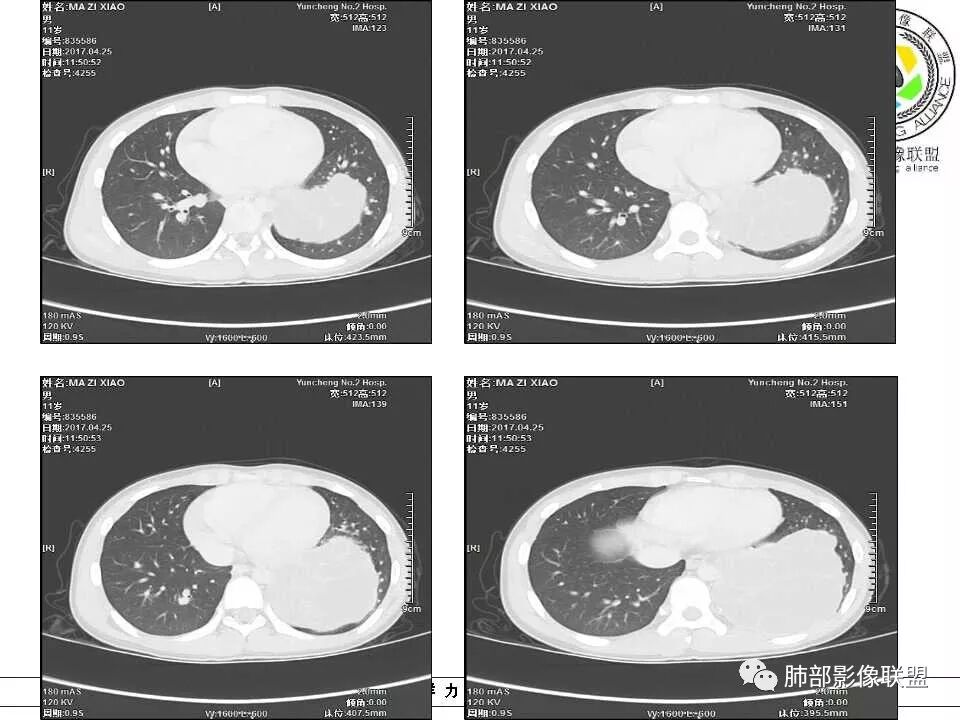

病例提供:运城市第二医院  王崇军

肺隔离症 膈下腹主动脉供血 肺静脉引流 多房改变支气管扩张积液?

左下肺囊性占位,多发分隔,增强分隔及边缘强化,腹主动脉供血,考虑肺隔离征。

儿童左下肺囊性占位,多发分隔,增强分隔可见强化,腹主动脉供血,肺隔离征。

左肺下叶病灶,囊性为主,内见分隔,边界清晰,首先考虑良性病变,增强可见体循环供血,考虑肺隔离症

儿童,左下病变,边界清,囊性,分隔明显,体循环供血,肺隔离症。

左下肺囊性团块灶,多发分隔,增强分隔及边缘强化,主动脉供血,考虑肺隔离症,叶外型。

左肺下叶囊性变,可见多发分隔,增强后分隔及边缘可见强化,并可见降主动脉分支进入,考虑叶外型肺隔离症

儿童,左下肺多房囊性占位,增强分隔强化,腹主动脉供血,肺隔离征。

11岁男患,左肺下叶见囊性病变,期内见分隔,增强扫描见强化,供血血管清晰,考虑肺隔离症,不除外多房性囊性病变。

男,11岁,左肺下叶囊性包块,形态不规则,内有分隔,包膜及分隔明显强化,主动脉供血,肺静脉引流,基底段支气管显示不清,首先考虑常见病肺隔离症,支气管囊肿不排除